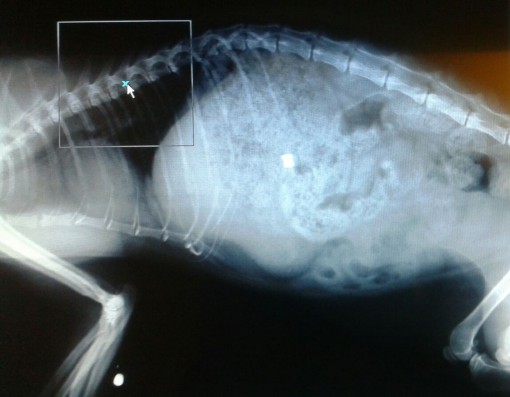

ABBADIA – Due pallini di piombo conficcati nel torace e nella zampa: è quanto è stato riscontrato dalle lastre effettuate su una gatta soccorsa la scorsa settimana ad Abbadia Lariana e trasportata d’urgenza da un veterinario per le cure del caso.

Se ancora non è chiaro come la gatta si sia procurata la ferita alla testa, è invece evidente che qualcuno l’abbia presa di “mira”, con una pistola d’aria compressa o con una carabina, ne sono testimonianza i pallini ritrovati nel corpo. A rendere noto l’accaduto è l’associazione Zampamica, i cui volontari si sono recati dai carabinieri di Mandello per sporgere denuncia formale.